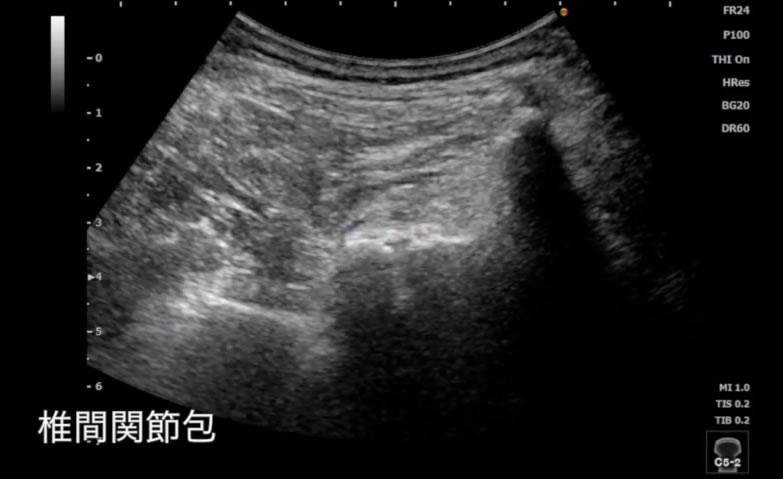

5.エコーガイド下 fascia(ファシア)リリース

当会では痛み、痺れ、肩こりなどへの対処方法としてエコーを画像の下でfasica(ファシア)へアプローチをする「エコーガイド下fasciaリリース®」の研究を進めております。

エコーガイド下fascia(ファシア)リリースには、以下が含まれます。

- 注射によるエコーガイド下fasciaリリース(=エコーガイド下fasciaハイドロリリースTM)

- 鍼によるエコーガイド下fasciaリリース

- 徒手によるエコーガイド下fasciaリリース

- 手術によるエコーガイド下fasciaリリース